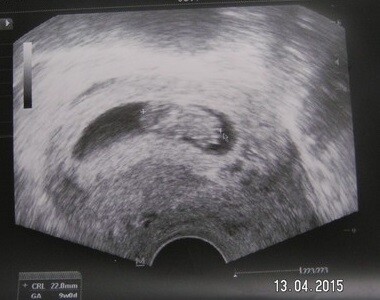

Silvia - Silvii je 25 let a je prvorodička. Po samovolném potratu se jí podařilo znovu rychle otěhotnět a nyní je ve 12. týdnu těhotenství. Za nedouho Silvii čeká vyšetření NT (nuchal transucency – projasnění záhlaví) a biochemický screening.